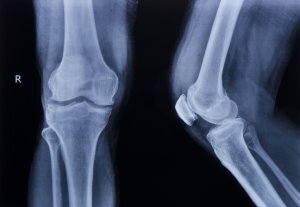

How Are Broken Bones Classified?

Broken bones get classified using several criteria:

Displaced or Non-Displaced

When your bone breaks, the broken ends might remain aligned. This happens in a non-displaced fracture.

But if enough force gets applied, the broken ends will move out of alignment. This type of fracture, called a displaced fracture, requires additional treatment before doctors can put a cast or brace on the injury.

Specifically, doctors must realign the bones in a displaced fracture through external manipulation or surgery. Depending on the location and nature of the break, doctors may even need to use screws and plates to hold the bone fragments in alignment so they can heal.

Open or Closed

A closed fracture is one that does not break the skin. You may see deformation in the area due to the fracture, but you will not see any open wounds or bones protruding.

An open fracture happens when the bone displaces so far that it breaks the skin. Also called compound fractures, these injuries have an increased risk of complications. Contamination can happen when chemicals, dirt, or other foreign substances get into your body. When that happens, an infection can result.

For an open fracture, doctors will set the bone by realigning its broken ends. They will clean the wound and stitch it closed to try to minimize the risk of contamination or infection.

Shape

Some fractures get defined by their shape. These fractures are also classified by whether the bone displaces or breaks through the skin. A simple displaced open fracture describes the shape, displacement, and whether it broke the skin.

Some shapes of fractures are listed below:

- A transverse fracture crosses the axis of the bone

- A spiral fracture circles the axis of the bone

- An impacted fracture happens when the bone gets compressed lengthwise

- A comminuted fracture occurs when the bone breaks into at least three parts

- An avulsion fracture happens when a ligament or tendon pulls off a piece of bone where it was attached

These shapes can affect whether you need surgery to repair the fracture and how long the bone will take to heal.